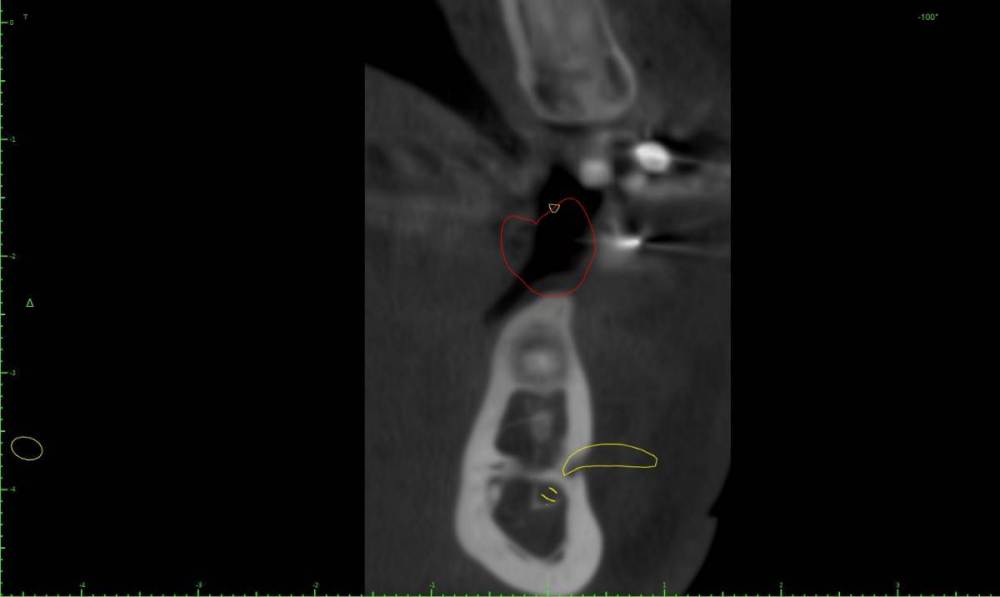

Женька Опубликовано 1 марта, 2022 Поделиться Опубликовано 1 марта, 2022 Коллеги помогайте. За качество КТ извиняйте, снимали весь череп разрешение упало у снимка. Как бы так достать его, чтобы имплантации не помешать одномоментной? Ссылка на комментарий

TIGER Опубликовано 3 марта, 2022 Поделиться Опубликовано 3 марта, 2022 @Женька вообще не парьтесь Ссылка на комментарий

Женька Опубликовано 3 марта, 2022 Автор Поделиться Опубликовано 3 марта, 2022 @TIGER в смысле? хотите сказать не трогать? просто преп и уйдет само? Ссылка на комментарий

TIGER Опубликовано 4 марта, 2022 Поделиться Опубликовано 4 марта, 2022 @Женька преп и после убрать 1 Ссылка на комментарий